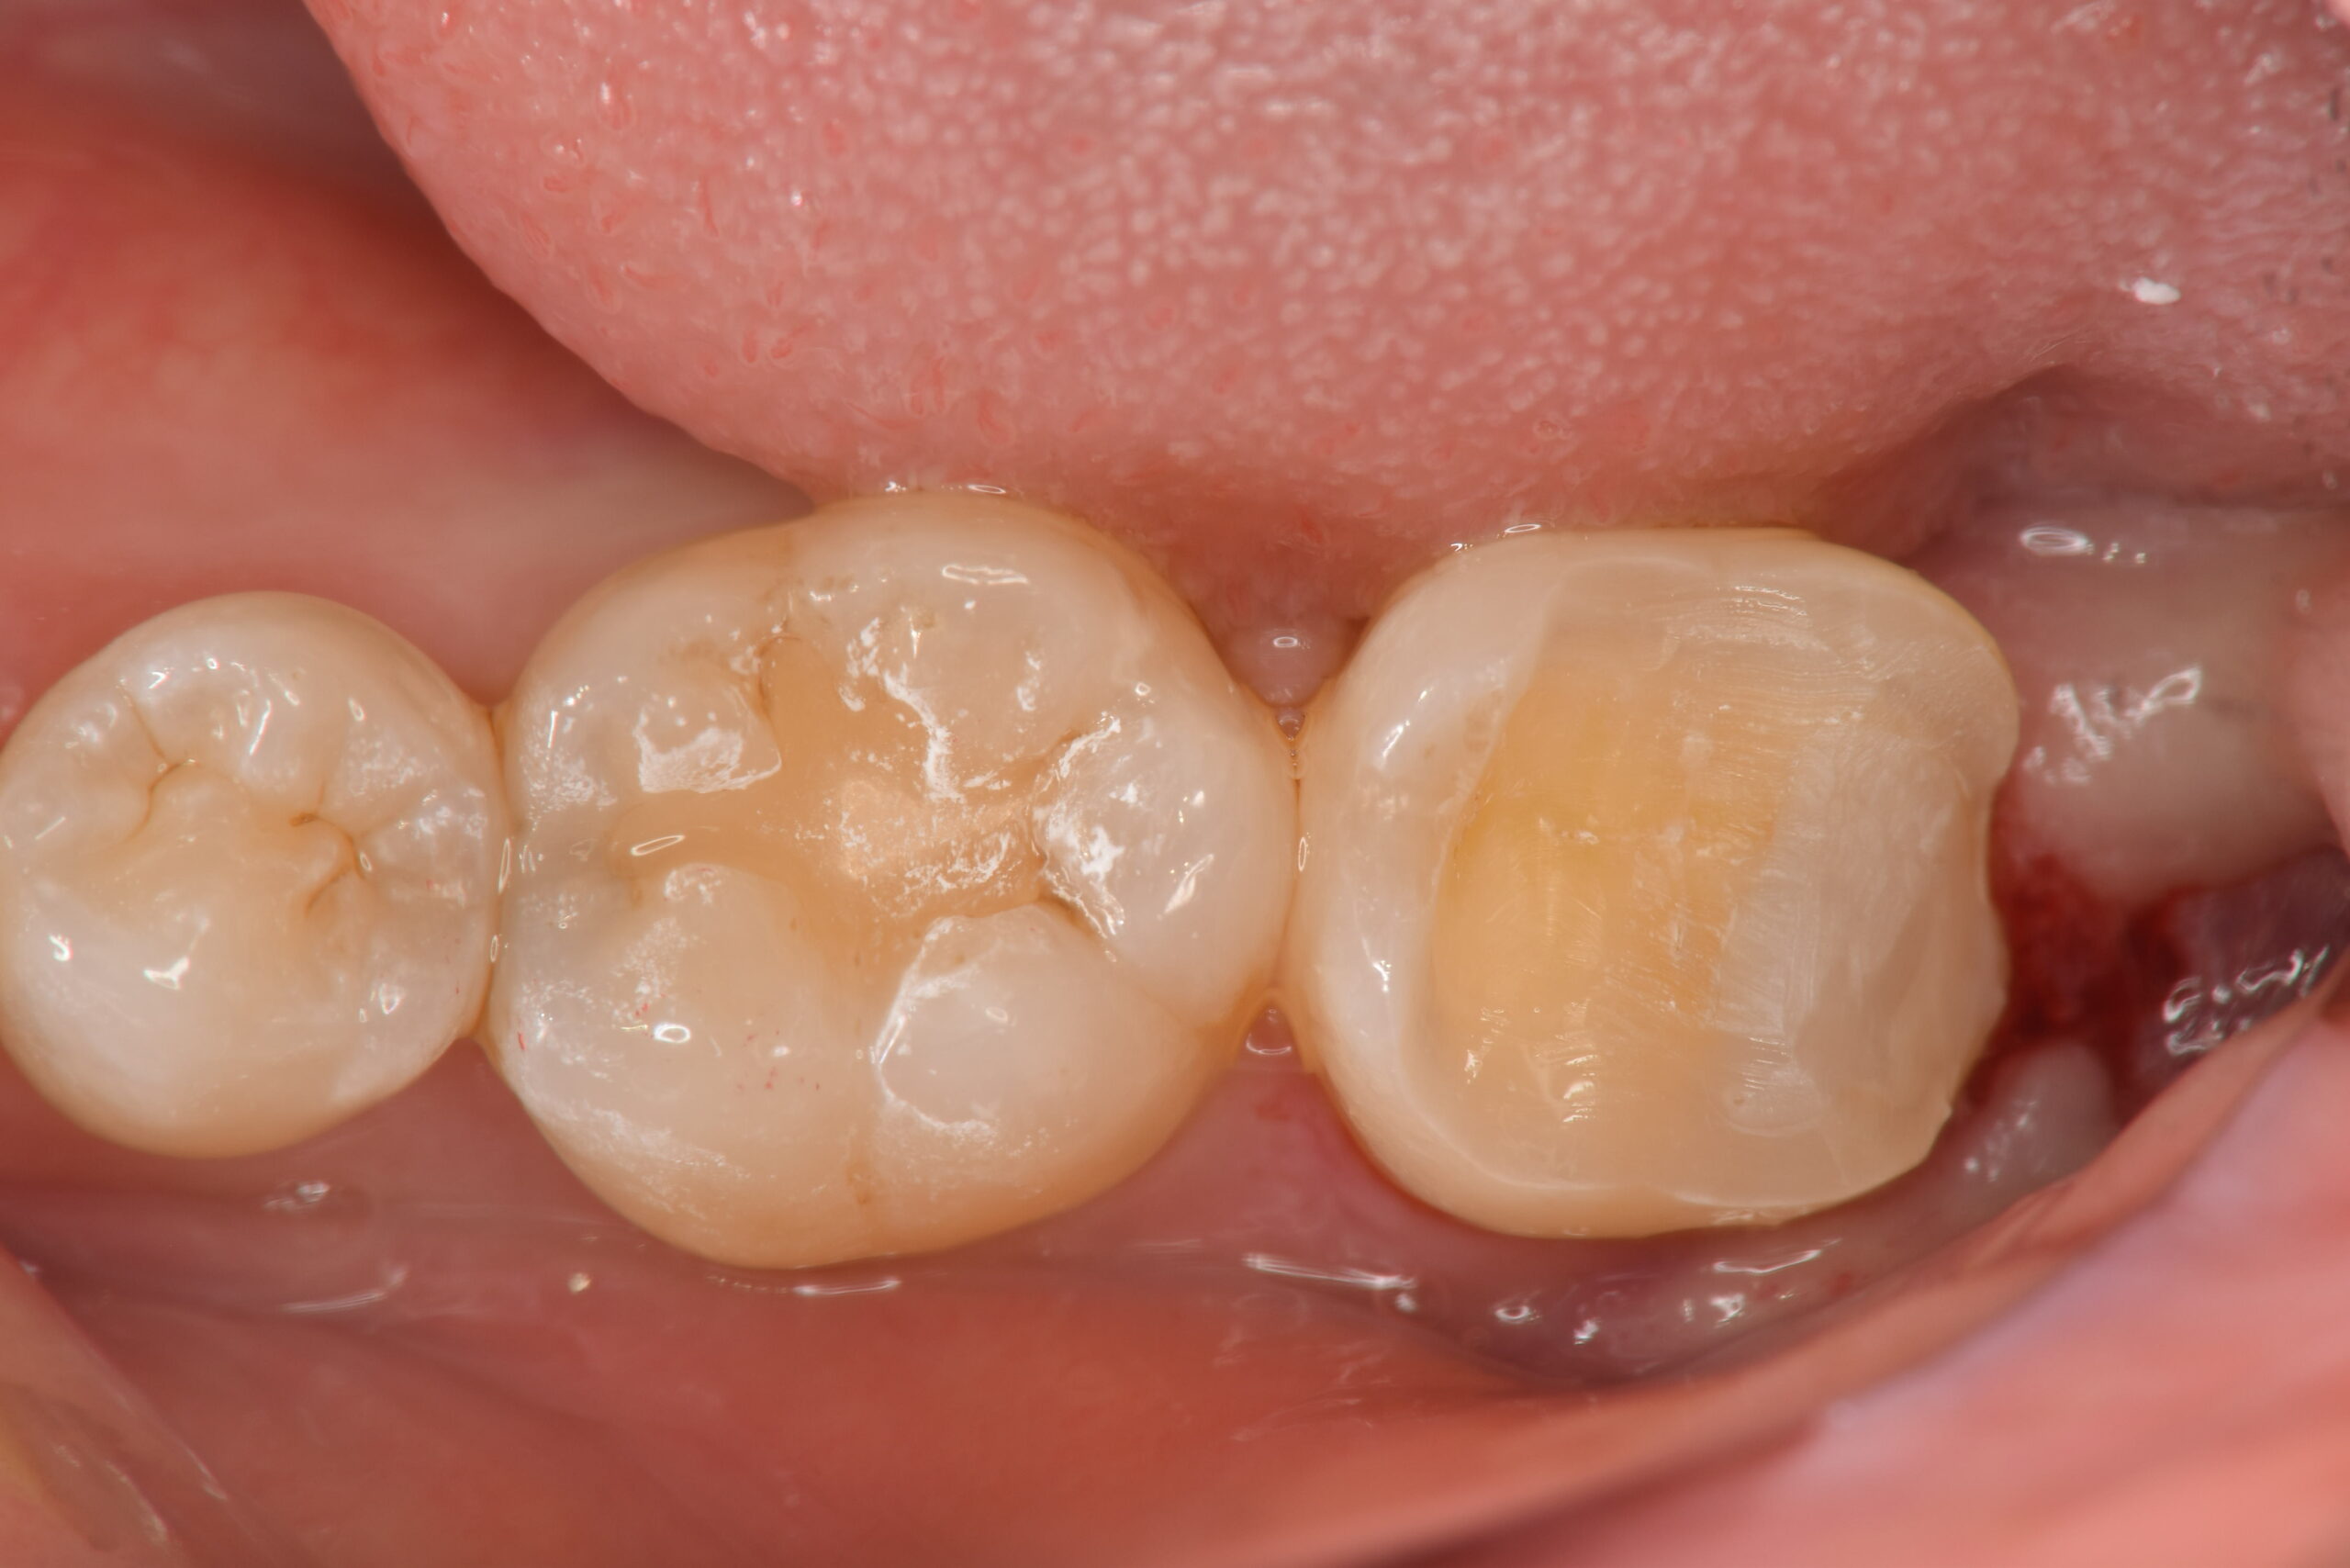

装着後のお写真です。横から見ても、全く隙間がないことが確認できます。

隙間がないことで、虫歯の再発予防に貢献してくれるでしょう。

MTAを用いたVPT(歯髄温存療法)から5ヶ月経過しておりますが、患者様は7番目の歯の痛みを訴えることなく検診に通われているため、経過は良好といえるでしょう。